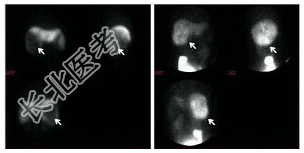

- [材料题] 男性,48岁,上腹部不适,AFP阴性,行⁹⁹Tcᵐ-Phy及⁶⁷Ga-枸橼酸钠显像如图: